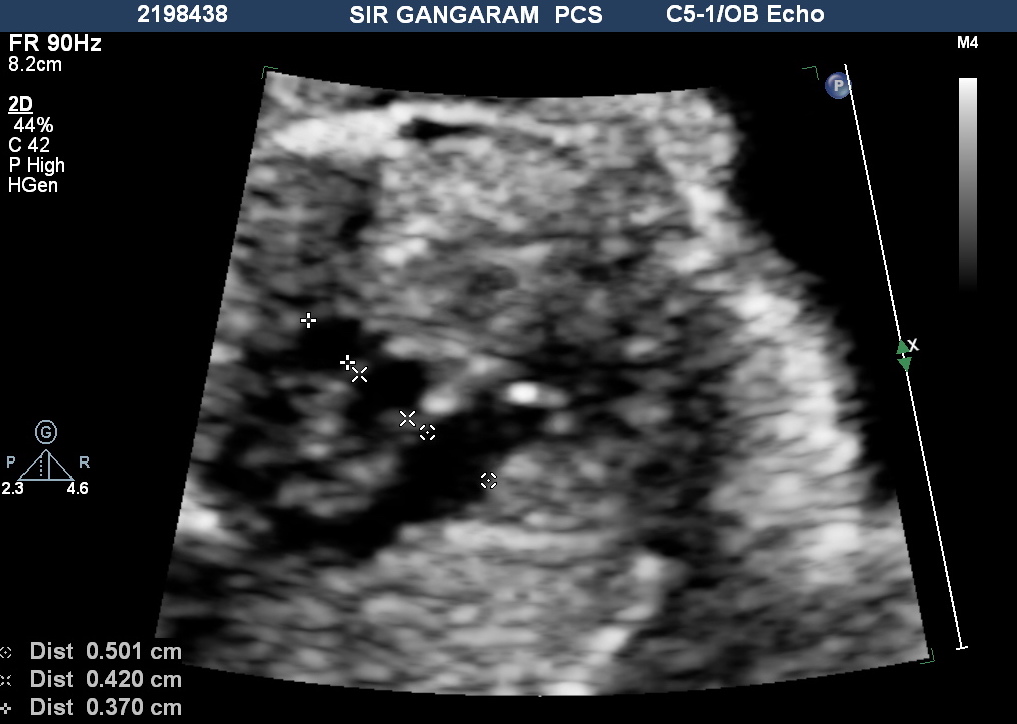

ID ratio is of significant interest because it is a relatively duration-independent parameter and it has significantly better specificity and positive predictive value. In the three vessels trachea view (3VT view), the internal diameter of the aortic isthmus was measured immediately proximal to the insertion of the ductus arteriosus and ductus at the distal-most point near insertion to descending aorta, inner margin to inner margin.

Matsui et al. showed that the isthmus to ductal ratio enabled good separation between their two groups. They used the 95% reference range of 0.74 to 1.23 for normal fetuses and an isthmus/ ductal ratio of < 0.74 for all fetuses who required surgery or surveillance after birth.

Study Gómez-Montes showed mean isthmus to the ductal ratio in normal fetuses of >0.7 and fetuses with post-natal coarctation it is <0.6 before 28 weeks and 0.5 in >28 weeks.

A retrospective study by Toole et al stated that an isthmus to the ductal ratio of <0.64 on any single fetal echocardiogram was nearly 90% sensitive and that <0.5 was 100% specific for postnatal coarctation.

Overall isthmus to ductal ratio is a good screening marker. When the ratio is above 0.74 without another additional marker of fetal coarctation, then the possibility of fetal coarctation is low. When the isthmus to ductal ratio is less than 0.74, the possibility of coarctation should be kept in the diagnosis. If the ratio is less than 0.6 in the first and second trimesters and less than 0.5 in the third trimester, the chance of CoA is very high. The parents in this situation should be counselled accordingly and delivery at a centre equipped with a pediatric cardiac unit should be recommended.